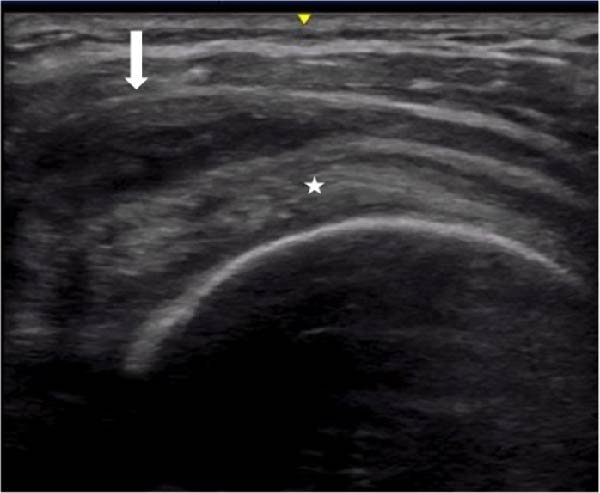

2) This study focuses on babies (infants aged 0 to 90 days) with suspected SARS-CoV-2 infections.

"Among 1048 infants tested for SARS-CoV-2, 432 (41.2%) were SARS-CoV-2โ€“positive and 616 (58.8%) were SARS-CoV-2โ€“negative.

Overall, 28 (2.8%) were noted to be moderately Image

3) ... or severely ill at presentation. There were 373 (35.6%) who underwent additional viral testing besides SARS-CoV-2, and other viruses were detected among 16 of 143 (11.2%) SARS-CoV-2โ€“positive and 82 of 230 (35.7%) SARS-CoV-2โ€“negative infants.

4) In terms of symptoms, "fever, cough, and upper respiratory symptoms were the most common symptoms among children with acute SARS-CoV-2 infections, with fewer lower airway symptoms compared with children with respiratory syncytial virus infections" Image

5) The only good news from this study (that differs from the results obtained in other studies) is that the overall number of presenting symptoms did not differ between groups.

The authors therefore concluded that "SARS-CoV-2 infections may be difficult to differentiate

6) ... from illness similarities among the youngest infants."

But whatever the results obtained which differ depending on the studies, can we accept that practically one in two sick babies in this study was contaminated by SARS-COV-2?